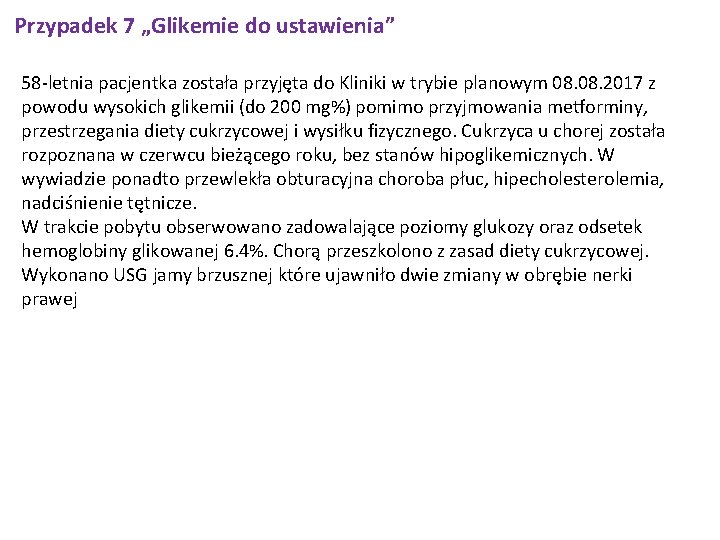

Przypadek 7 „Glikemie do ustawienia” 58 -letnia pacjentka została przyjęta do Kliniki w trybie planowym 08. 2017 z powodu wysokich glikemii (do 200 mg%) pomimo przyjmowania metforminy, przestrzegania diety cukrzycowej i wysiłku fizycznego. Cukrzyca u chorej została rozpoznana w czerwcu bieżącego roku, bez stanów hipoglikemicznych. W wywiadzie ponadto przewlekła obturacyjna choroba płuc, hipecholesterolemia, nadciśnienie tętnicze. W trakcie pobytu obserwowano zadowalające poziomy glukozy oraz odsetek hemoglobiny glikowanej 6. 4%. Chorą przeszkolono z zasad diety cukrzycowej. Wykonano USG jamy brzusznej które ujawniło dwie zmiany w obrębie nerki prawej